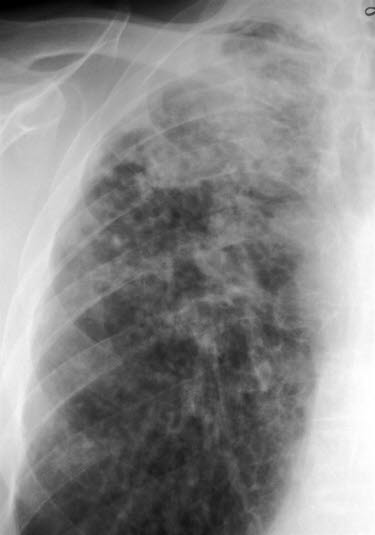

Lungefibrose (HRCT)Lungefibrose er en tilstand med betennelse og økt mengde bindevev (arrvev) i lungene. Arrdannelse er kroppens måte å reparere vevsskade på, ikke bare i lungene, men i hele kroppen. Det er sammenlignbart med et arr i huden etter et skrubbsår. Ved lungefibrose er det unormal arrdannelse i lungeblærene. Når det dannes arr isteden for normalt lungevev, blir gassutvekslingen mellom lunge og blod dårligere enn normalt. Lungene blir stivere og mindre bevegelige, og det arealet som kan brukes til gassutveksling, minker. Har man lett grad av lungefibrose, er det ikke sikkert man merker det på pusten, men jo mer fibrose som dannes, jo tyngre blir det å puste.

Legen foretar en fysisk undersøkelse og tar blodprøver for å komme nærmere diagnosen. Lungefunksjonsprøver (spirometri) kan si mye om hvilken type lungesykdom det dreier seg om. Lungefibrose vil nesten alltid vises på et røntgen-/CT-bilde av lungene. Dersom man fortsatt er i tvil etter røntgen/CT, kan man ta en vevsprøve fra lungene og undersøke denne i et mikroskop.